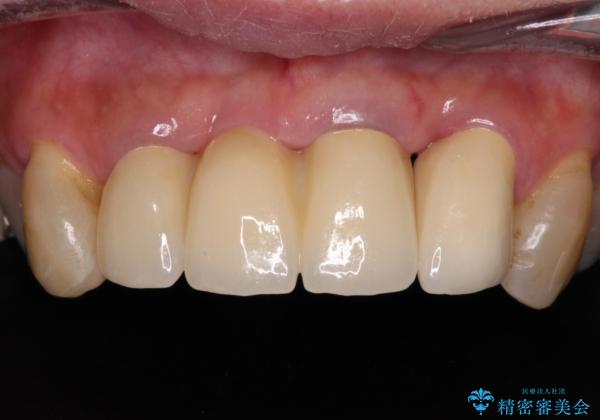

不具合ばかりの前歯 前歯のオールセラミックブリッジ

- 上顎前歯の違和感や不快感を気にして来院された患者様です。

現在のクラウンは金属の縁が見えており、歯と歯と歯肉の間に大きなスペースができていて、見た目も悪く、物が挟まったり話しにくかったりしていました。

また、前歯に抜歯が必要な歯があったため、抜歯をし、傷の治りを待ってオールセラミックブリッジにて補綴治療を行うこととしました。

一番気になっていた隙間が埋まり、不快感から解放されました。